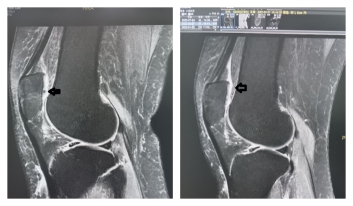

03-21 21:00...此前存在的软骨缺损区域已得到明显修复,几乎消失。与此同时,患者的膝关节疼痛感大幅缓解,关节活动功能显著改善,生活质量有效提升。PRP技术原理:提取自身的“修复兵团”PRP,全称为富血小板血浆,其核心原理属于“自体生物治疗”。治疗时,医务人员只需从患者手臂抽取少量静脉血,然后通过专用的离心设备进行分离、浓缩,最终得到血小... 0